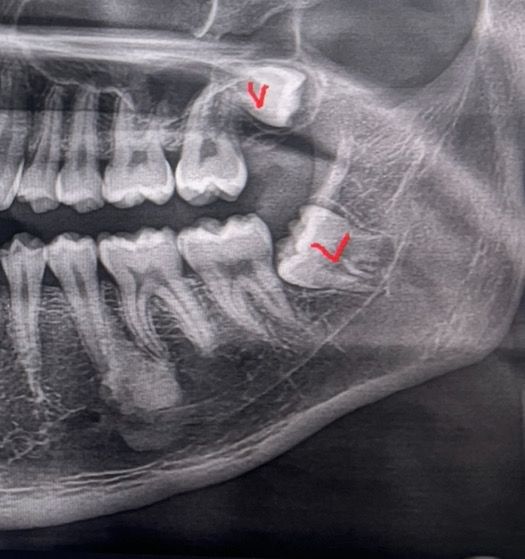

매복사랑니 6일차 통증 드라이소캣인가요?

저번주 토요일 왼쪽 아래 매복사랑니 뽑고 6일차입니다 보통 이쯤되면 텅증도 없고 괜찮다는데 전 병원에서 처방해준 약을 먹으면 안아프고 멀쩡한데 약기운이 떨어지면 욱신거리고 뛰는느낌?들고 아파요

드라이 소캣인가요? 참고로 술담배 안합니다 밥은 첫날은 죽 먹다가 죽도 못먹겠어서 굶고 둘째날부터 약 먹으면서 일반식 먹었습니다 원래 통중이 이렇게 오래가나요? 피나거나 그런건 없는거같아요 입안을 보고싶은데 어두워서 잘 안보입니다

매복사랑니라 잇몸도 절개를 하고 잇몸뼈도 삭제를 해서 발치를 해서 통증이 오랫동안 지속되는거 같습니다.

드라이소켓은 통증의 강도가 높기 때문에 엄청 아픈것이 아니라면 드라이 소켓은 아닐것으로 생각됩니다.

드라이소켓은 애매한 통증 아니고 아주 극심한 통증과 함께 악취가 납니다 발치 후 1~2주는 원래 통증이 있을 수 있으니 통증 있을때 소염진통제 드시기 바랍니다